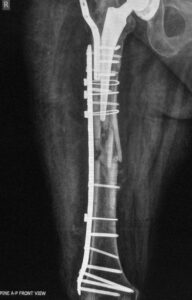

- Περιπροθετικό κάταγμα στην περιοχή στο πέρας του εμφυτεύματος ισχίου σε θήλυ ασθενή .

- Εσωτερική οστεοσύνθεση με πλάκα με αλληλοεπικάλυψη των εμφυτευμάτων για να μην υπάρχουν υψηλές συγκεντρώσεις φορτίων (stress risers)

- H οστεοσύνθεση σε οστεοπορωτικoύς ασθενείς αρχίζει από το γόνατο με σωστή εφαρμογή του εμφυτεύματος και φθάνει μέχρι το ισχίο για να μην υπάρχουν stress risers.

Tα περιπροθετικά κατάγματα σε ηλικιωμένους πρέπει στην οστεοσύνθεση να περιλαμβάνουν ολόκληρο το μήκος του οστού, με αρκετή ελαστικότητα, προάγοντας έτσι την πώρωση και διατηρώντας ταυτόχρονα την σταθερότητα του συστήματος.